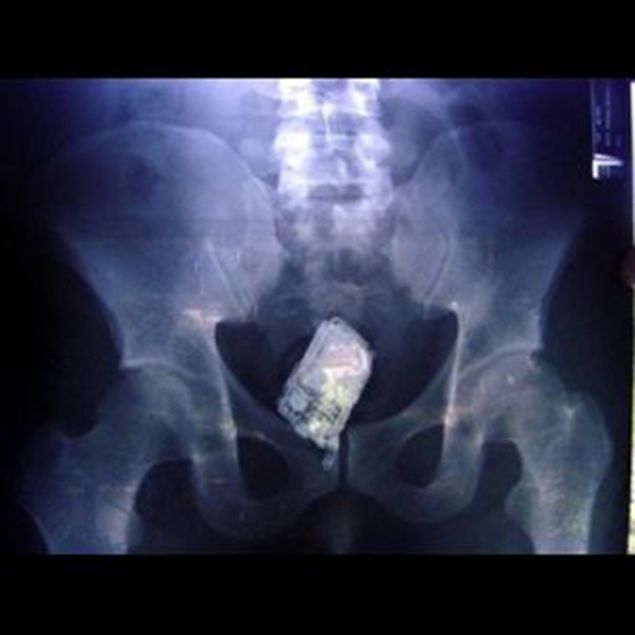

Lista rusinoasa a radiografiilor inedite este completata de imagini cu o vanata, o jucarie de plastic, un deodorant sau chiar un telefon mobil! Toate aflate "captive" in aceeasi zona a corpului.